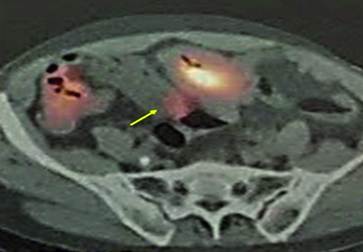

El paciente presenta rectorragias autolimitadas, por lo que se realiza colonoscopia encontrando ulceraciones colónicas sin sangrado activo y PET-scan donde se objetiva captación compatible con tumoración tipo GIST (Figura 2).